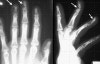

X-ray : 원위 지골 골절(distal phalanx fracture)

크게 tuft 골절, 간부(shaft) 골절, 관절내(intra-articular) 골절로 나눌 수 있습니다.

기저부에서의 골절은 굴근이나 건 손상과 동반될 수 있습니다.

손톱 바닥 손상이나 조갑하혈종이 동반되었는지 관찰합니다.

치료는 일반적으로 splint(hairpin splint or finger splint)로 고정시킵니다.